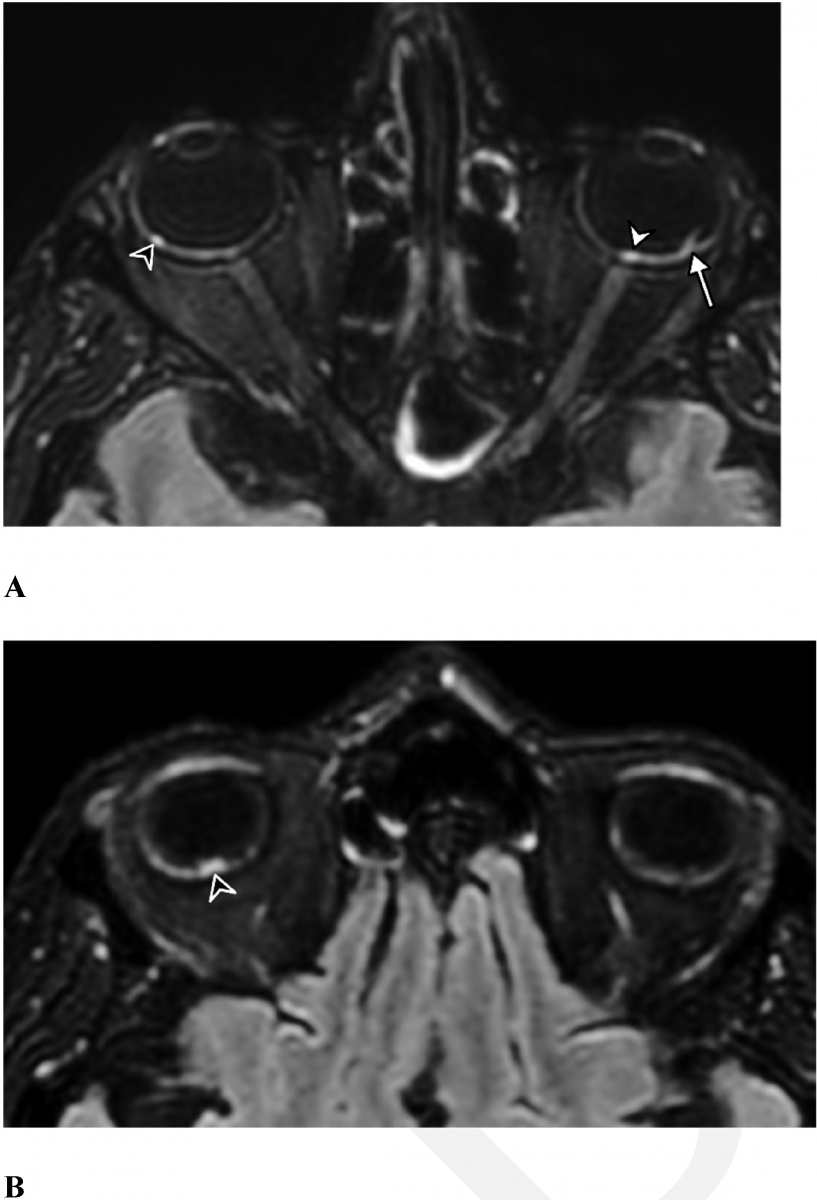

- Nine of these patients (a statistically significant seven per cent) had abnormal MRI findings of the globe, or eyeball.

- All nine patients had nodules in the macular region and eight had nodules in both eyes.

That the “potentially dangerous” nodules were found in the macula, part of the retina at the back of the eye, is especially concerning. It is about 5mm across but is responsible for our central vision, most of our colour vision and the fine detail of what we see.